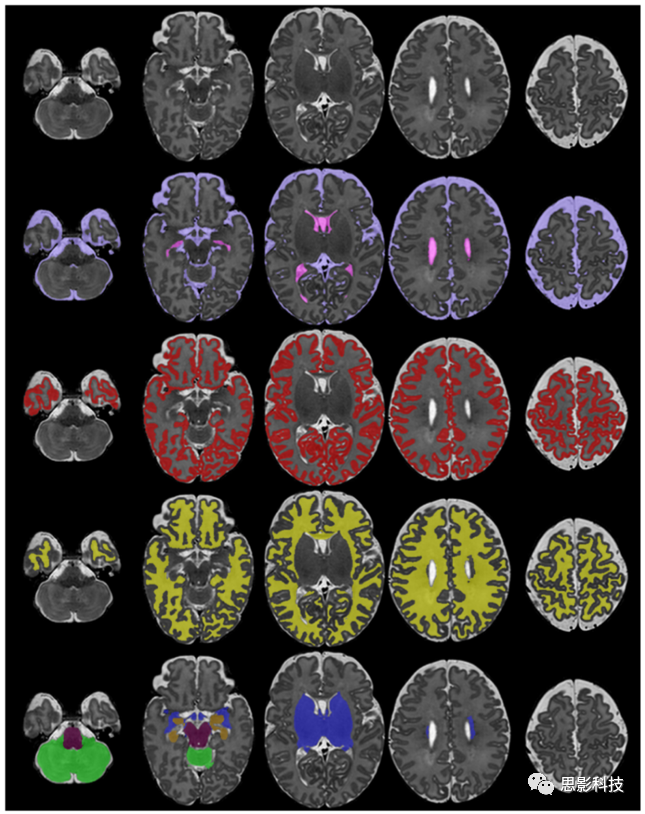

在新生兒分割領(lǐng)域的研究主要集中于腦MR圖像的組織分割。本節(jié)介紹文獻(xiàn)中用于新生兒組織分割的方法。圖7給出了不同組織類型的分割示例。

8.3. 結(jié)構(gòu)分割

對大腦局部結(jié)構(gòu)的繪制比較困難,這是因為缺乏細(xì)致的的手工分割圖譜。早期的方法是基于人工放置在腦軸上的CGMWM區(qū)域的分割。這些軸將CGM / WM分為16個部分:額葉、中央前、中央和枕骨區(qū),分為左右半球的上半部和下半部。Oishi等人(2011)和Gousias等人(2012)手動描繪了大腦的第一個區(qū)域圖譜?,F(xiàn)有的分割方法使用這些圖譜或從成人圖譜中的label來描繪嬰幼兒大腦的區(qū)域結(jié)構(gòu)。使用成人大腦結(jié)構(gòu)的label進(jìn)行分割可能會出現(xiàn)問題,因為發(fā)育中的大腦可能尚未形成不同的大腦結(jié)構(gòu)。圖8中展示了了分割為不同結(jié)構(gòu)的示例。

使用Draw-EM的新生兒MRI的組織分割示例。

8.使用Draw-EM的新生兒MRI結(jié)構(gòu)分割的示例。